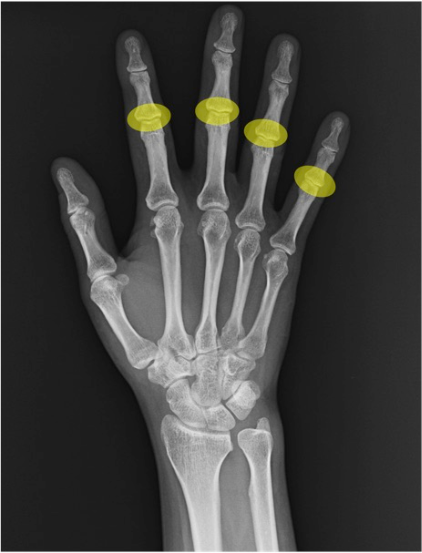

PIP関節(proximal interphalangeal joint)

第2~5指の近位指節間。PA像で裂隙均等性、側面像で関節面平行性を確認。変形性変化や外傷性変化のファーストチェックポイント。